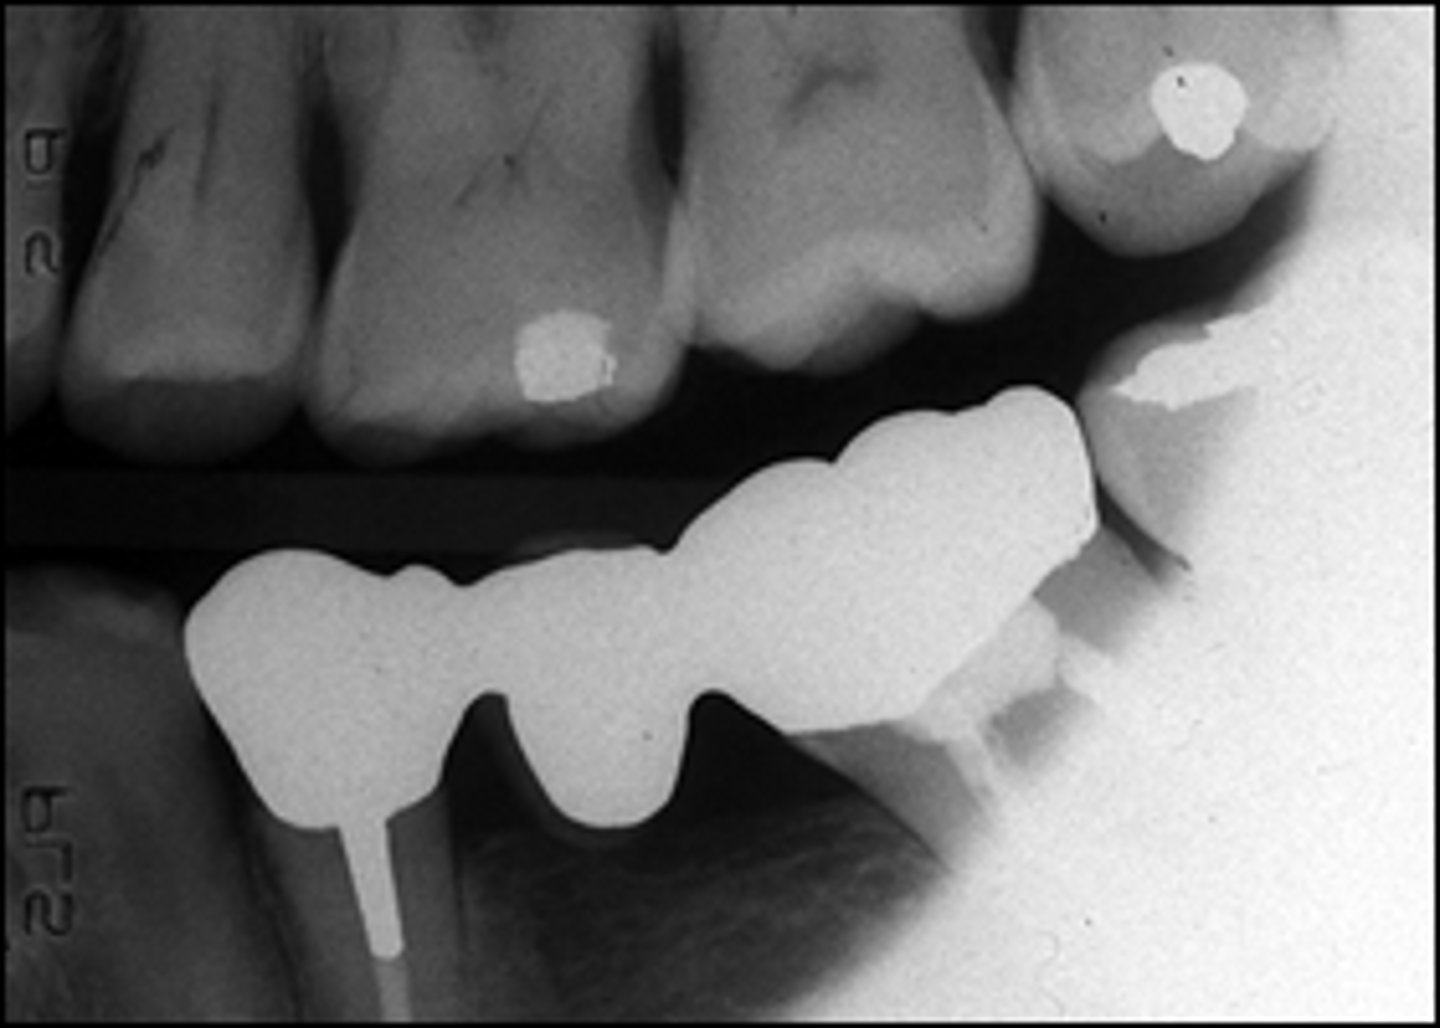

cause film to be too light, fogged, or tinted brown

exhausted fixer pictured